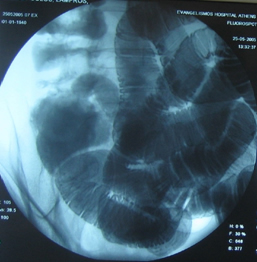

Στους ίδιους ασθενείς η εντερόκλυση μπορεί να αναδείξει ανάλογα ευρήματα με την ενδοσκοπική κάψουλα (εικόνες 36-43) ή να είναι φυσιολογική (εικόνες 44-48).

36  37

Εικόνες 36, 37. Ο ίδιος ασθενής με τις εικόνες 15, 16. Εικόνα πλακόστρωτου με στένωση και παρουσία        βαθιάς εξέλκωσης του βλεννογόνου